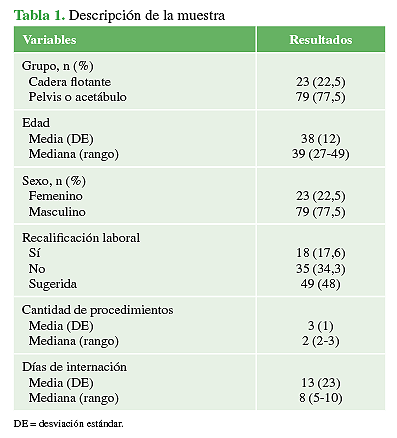

Se incluyó a 102 pacientes con trauma de pelvis o acetábulo reunidos en dos grupos según la presencia de CF (CF: 23 pacientes, pelvis/acetábulo: 79 pacientes). En la Tabla 1, se resume la descripción global de la muestra.

Con respecto a los pacientes del grupo 1 (CF), el 60,9 % (n = 14) eran hombres y el 39,1%, mujeres (n = 9), con un promedio de edad de 30 años (DE = 10). El mecanismo de lesión fue la colisión de motocicleta contra automóvil (78,2%, n = 18), automóvil contra automóvil (13%, n = 3) y caída de propia altura (8,8%, n = 2). El 60,8% de los pacientes (n = 14), tenía una clasificación tipo A de Liebergall; el 30,45% (n = 7), tipo B y el 8,7% (n = 2) tipo C. El tiempo promedio de seguimiento fue de 4.6 años (rango 1.2-5).

En relación con el grupo 2 (n = 79), el 82,3% (n = 65) eran hombres y el 17,7% (n = 14), mujeres. El promedio de edad era de 41 años (DE 12). En esta población, el 77,2% (n = 61) tenía fracturas de pelvis: 25 Tile A, 28 Tile B y 8 Tile C. El resto (22,8%, n = 18) tenía fracturas de acetábulo, que clasificadas según Judet incluyeron: 4 tipo A, 3 tipo B, 5 tipo C y 6 tipo D.

La mediana del tiempo de seguimiento fue 4.5 años (rango 1.2-5), la de días de internación, de 7 (rango 5-9) y la de la duración de los procedimientos ortopédicos realizados, de 132 min (rango 90-252). En relación con la cantidad de procedimientos ortopédicos por paciente, la mediana fue de 2 (rango 2-3). Se constató una mediana de pérdida hemática de 320 ml (rango 250-700).

En este subgrupo de la muestra, la mediana de procedimientos quirúrgicos por paciente fue de 3 (rango 1-8), con una media de 2,99 (DE 1,5). La mediana de días de internación fue de 8 (rango 3-193), con una media de 15.12 días (DE 26,9).

Al analizar estas variables en la comparación entre pacientes con CF frente a aquellos con fractura de pelvis/acetábulo, las medianas de días de internación [CF 15,5 (rango 4-193); pelvis/acetábulo 7 (rango 3-31); p = 0,0001] y de la cantidad de cirugías por paciente [CF 5 (rango 3-8); pelvis/acetábulo 2 (rango 1-4); p = 0,0001] fueron mayores en los pacientes con CF, con diferencia estadísticamente significativa en la distribución de ambas variables (Figura 9).